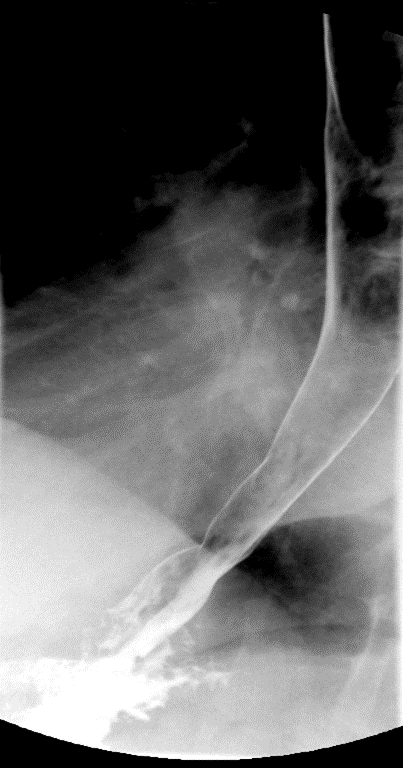

- Method—Cervical:

- Start with the patient in the upright lateral position.

- Once the patient has taken the "comfortable mouthful" of barium, center the fluoroscope on the cervical esophagus.

- Once the fluoroscope is properly positioned, begin counting. On the count of 2, begin taking rapid sequence images of the contrast material bolus as it moves through the cervical esophagus

(key image 1)

- With the patient in the lateral position, obtain a spot film of the pharynx and cervical esophagus while they phonate the letter "e"

(key image 2).